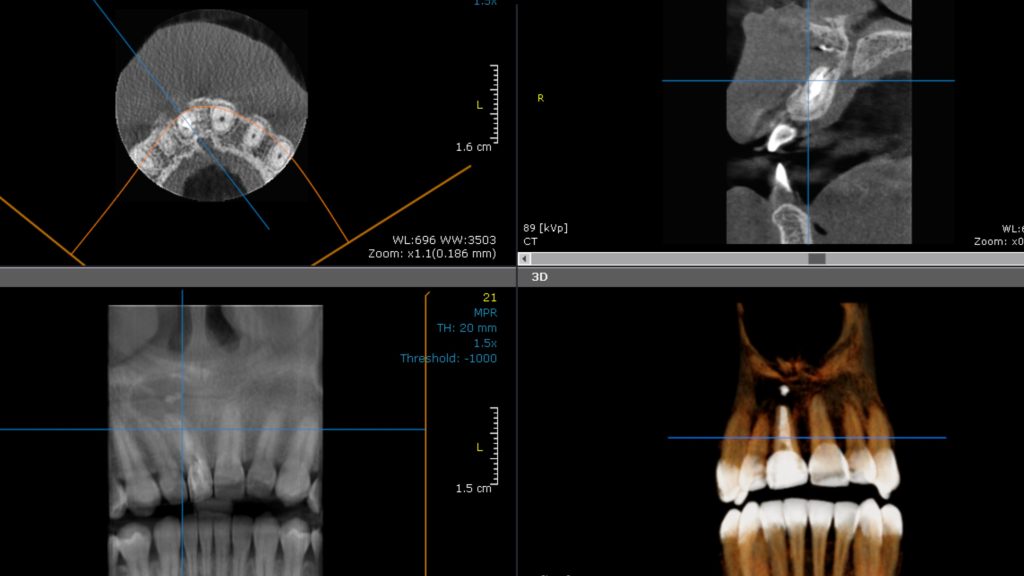

Surgical stage